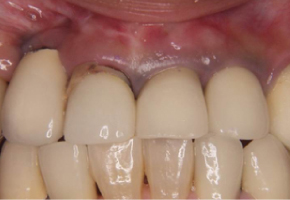

歯肉の変色を除去し補綴処置後

歯肉が金属片の影響で変色

初診時に歯肉に金属等が迷入して黒ずんでいるケースでも、マイクロスコープを使用して強拡大下の低侵襲で歯肉中の金属等を除去することが可能なケースもあります。その後再度補綴処置を行って審美性の向上を得られます。まれに、歯肉レベルに変化がおこなることもあります。